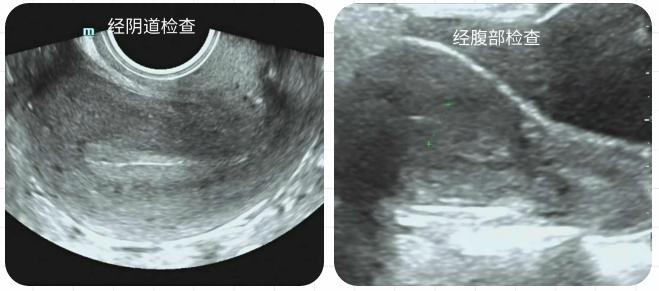

2.從圖像的質(zhì)量來說,肯定是陰超圖像更細(xì)膩更清楚,一些小的部位的觀察,比如內(nèi)膜息肉、宮內(nèi)早早孕、輸卵管妊娠、卵巢扭轉(zhuǎn)、小肌瘤等,陰超能更早發(fā)現(xiàn)、診斷也更準(zhǔn)確。這里要突出一個(gè)早字,越早發(fā)現(xiàn)越能及時(shí)處理,增加一些治療上的選擇性及主動性,避免后期被動性從而降低一些隱患風(fēng)險(xiǎn)。而腹部超聲圖像的質(zhì)量跟受檢者的腹壁厚度的影響,越厚顯示越不清楚。有人打趣的說過,一個(gè)是在屋外觀察一個(gè)是屋內(nèi)直接觀察,您說哪個(gè)清楚?

3. 當(dāng)然陰超也是有限制的,比如沒有性生活的女孩、陰道接觸性出血、比較嚴(yán)重炎癥患者都不適合陰道超聲,那就只能腹部。有時(shí)候陰道檢查還需要同時(shí)結(jié)合腹部檢查來完善結(jié)果。對于較大包塊的測量及整體觀察,腹部掃查范圍更廣更有優(yōu)勢。